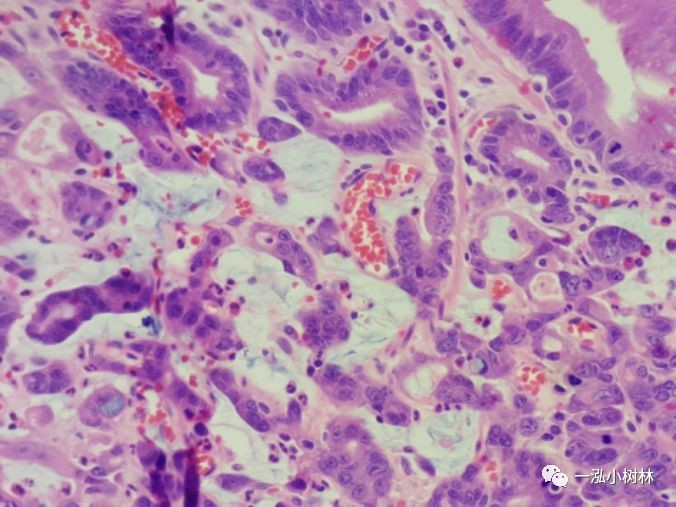

萎缩性胃炎是Hp感染胃黏膜中一种特征性胃炎。胃黏膜萎缩、肠上皮化生是发生分化型胃癌的背景。分化型胃癌发生的基本过程:正常胃黏膜——浅表性胃炎--萎缩性胃炎--肠化生-不典型增生--分化型胃癌。认识萎缩性胃炎、肠上皮化生对一个内镜医师至关重要。

萎缩性胃炎普通内镜表现:黏膜苍白,黏膜下血管透见,黏膜皱襞细小或消失,病变黏膜粗糙呈颗粒状或结节状,伴有肠化时轻者常不可见,重者可见斑片状、点状米粒大小白色或灰白色隆起改变,另外萎缩黏膜与正常黏膜可见到萎缩边界。

NBI+ME内镜表现:萎缩区域NBI放大可见胃小凹消失或不清晰,树枝状血管显露,黏膜苍白及萎缩边界更明显,多以幽门胃窦部为中心,随着萎缩的加重,胃体黏膜也散见,肠化区域可见胃小凹呈绒毛状,可见到“亮蓝嵴”“白色不透明物质”征。